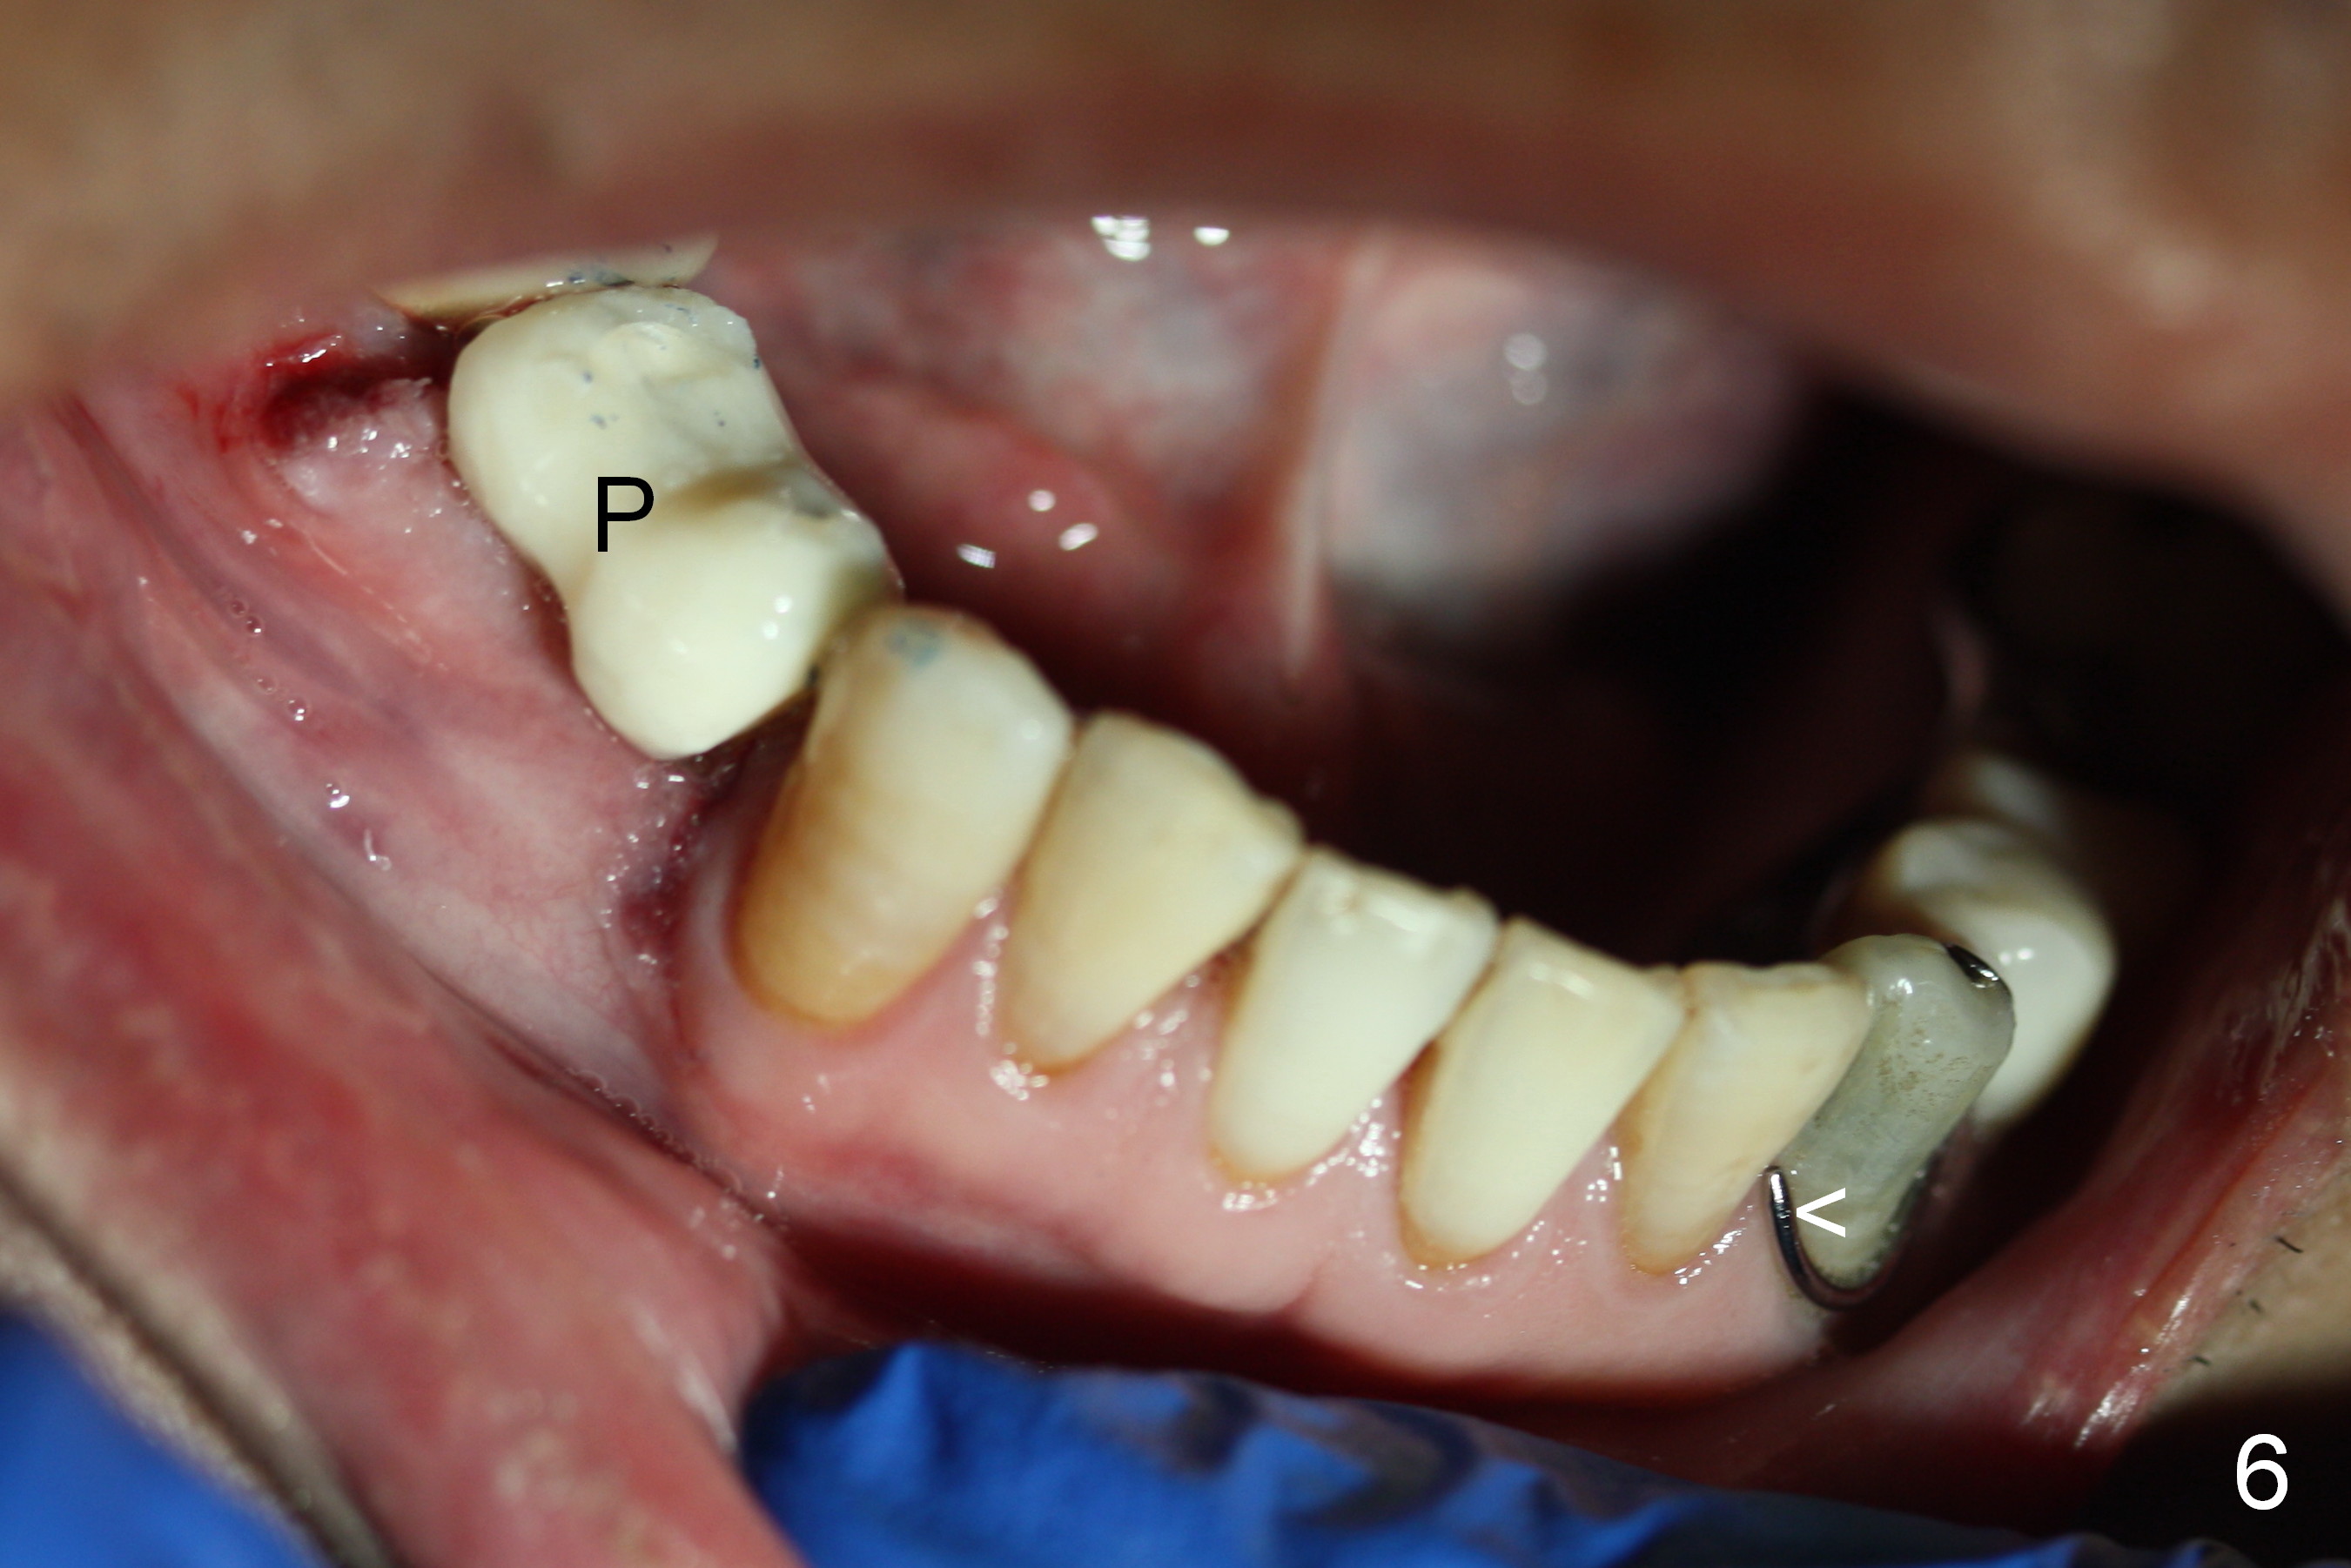

The 1st intraop PA taken after initial osteotomy at the depth of 12 mm shows that the mental loop (Fig.4 red dashed line) appears to be more superior than what is expected from CBCT study; while the apical end of the osteotomy at #28 is going to be moved mesially (>), that at #29 distally (<). Both implants (3x14 and 4.5x12 mm) are placed with insertion torque 56 Ncm (Fig.5). After placement of a 5.8x4(2) mm abutment at #29, an immediate provisional is fabricated and cemented (Fig.6 P). The partial is modified and the left portion is seated (Fig.6 <). The patient is pleased with the change: from removable to fixed appliance. There is no paresthesia postop.